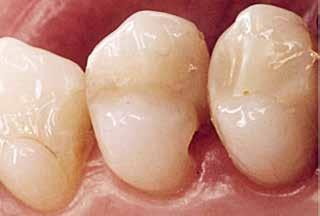

En dybtliggende amalgam-misfarvning udgør en af de mest vanskelige udfordringer ved udskiftning af restaureringer. Transcend Universal Body farven blev anvendt til at erstatte amalgamen, uden brug af blokeringsmateriale. Bemærk, hvor fremragende farven blender ind i den bevarede crista obliqua.

Før Efter